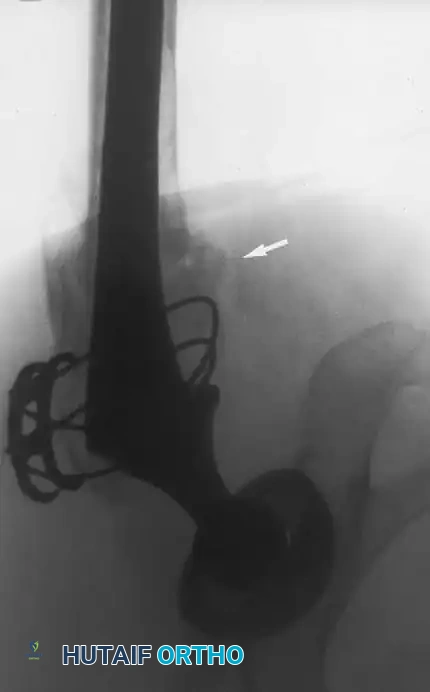

The Extended Trochanteric Osteotomy (ETO)

For complex femoral revisions, particularly those involving well-fixed cementless stems, varus remodeling, or extensive distal cement mantles, the Extended Trochanteric Osteotomy (ETO) is the gold standard.

Biomechanics of the ETO:

Unlike a standard trochanteric osteotomy, the ETO preserves the insertion of the gluteus medius and minimus proximally, and the origin of the vastus lateralis distally. This maintains a continuous myofascial sleeve, providing dynamic stability to the osteotomy fragment and dramatically improving union rates (typically >95%).

ETO Technique:

1. Measure the required length of the osteotomy preoperatively (usually 12-15 cm, ensuring it bypasses the well-fixed portion of the stem).

2. Elevate the vastus lateralis anteriorly to expose the lateral femur.

3. Use an oscillating saw or high-speed burr to make the posterior and anterior longitudinal cuts.

4. Complete the distal transverse cut, ensuring rounded corners to prevent stress risers.

5. Lever the fragment open anteriorly, hinging on the intact anterior periosteum and vastus lateralis.

Pitfall: When seating a diaphyseal-engaging stem, prophylactic cerclage cabling of the distal femur is highly recommended to prevent catastrophic intraoperative splitting of the diaphysis during final impaction.